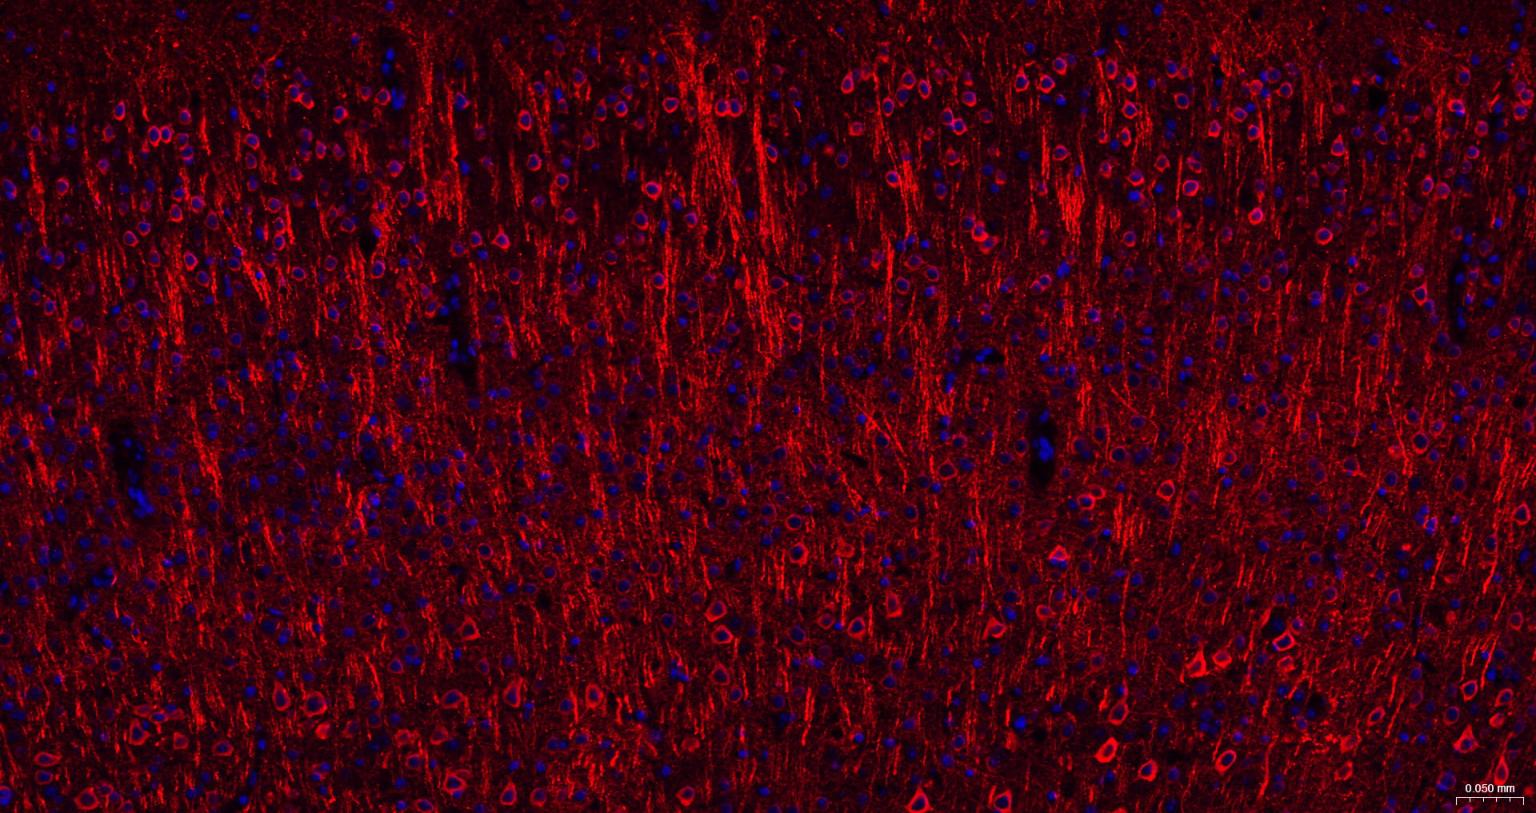

Paraformaldehyde-fixed, paraffin embedded Human Cerebrum; Antigen retrieval by boiling in sodium citrate buffer (pH6.0) for 15 min; The section was incubated with phospho-MAP2 (Ser136) Monoclonal Antibody, Unconjugated (bsm-62863R) at 1:200 overnight at 4°C. Followed by conjugated Goat Anti-Rabbit IgG antibody (Red, bs-0295G-BF594), DAPI (blue, C02-04002) was used to stain the cell nuclei.